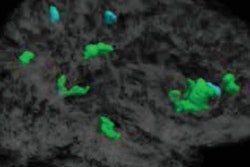

What's more, patients who underwent treatment had a considerably smaller hippocampus on MRI scans -- a part of the brain that helps regulate memory and spatial learning -- than those who did not.

Radiation affects the brain's ability to produce new neurons in the hippocampus, which, in turn, limits its ability to form new memories, noted lead author Melanie Sekeres, PhD, in release from the university.